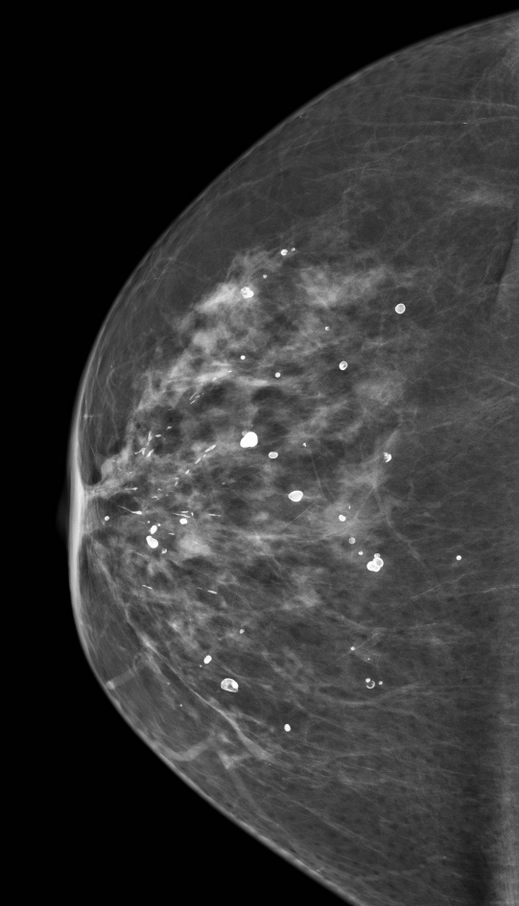

Vôi hóa dạng tròn (Round breast calcifications)